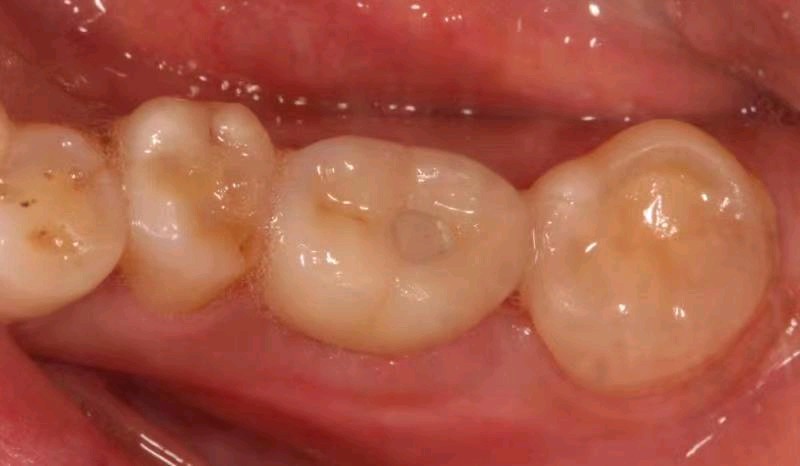

患者右下后牙根管治疗十年后咬合不适,x片显示近中根尖阴影较大,根折,患牙不能保留,患者非常焦虑拔牙,更怕种植牙,要求拔牙后即刻种植,通过CBCT检查,确定剩余骨量足够多,可以即拔即种植;患者知情同意下,完成即拔即种,四个月后CEREC数字化扫描,当天完成了牙冠修复,同时邻牙也完成嵌体修复!有图有真相。